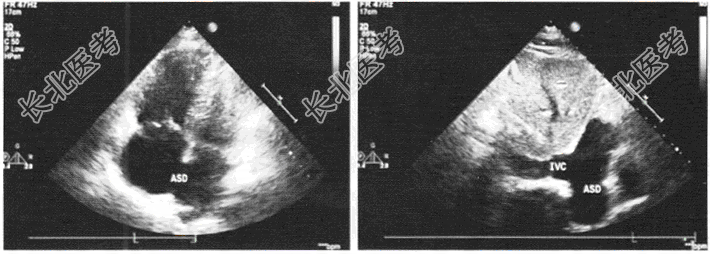

- 单项选择题患者,女性, 22岁,既往发现房间隔缺损, 来我院复诊,超声心动图如图所示, 其房间隔缺损是哪种类型

A、原发孔型

B、冠状窦型

C、上腔型

D、下腔型

E、中央型